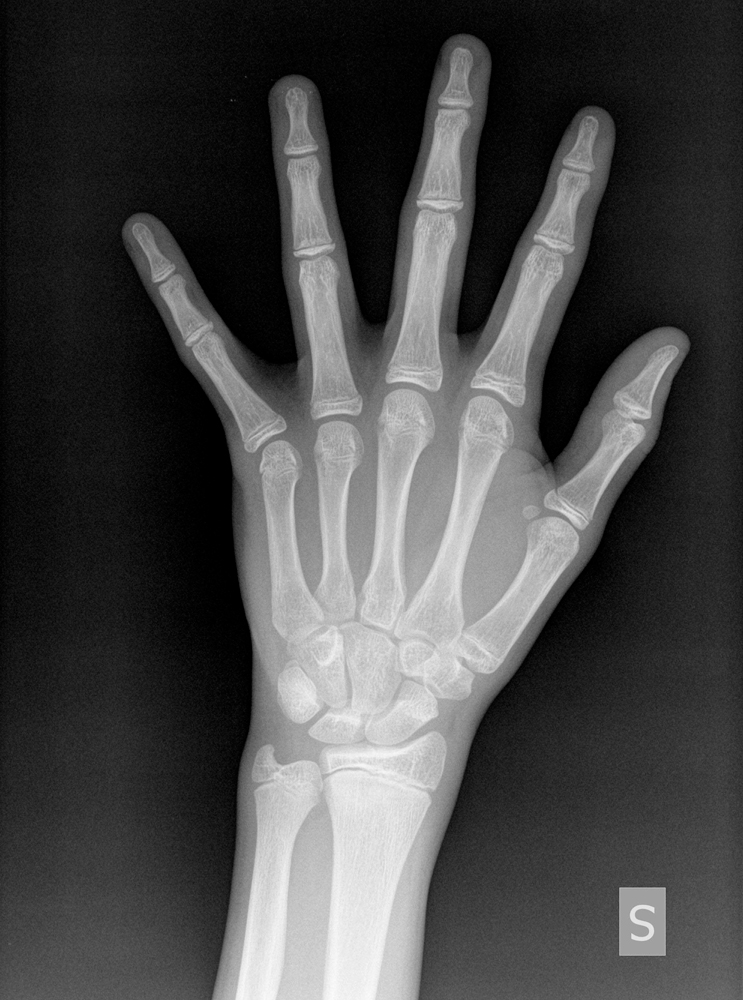

LA RADIOGRAFIA DELLA MANO

La radiografia della mano permette di definire l’età ossea con un margine di errore di circa 6 mesi. Per la datazione si fa riferimento solitamente all’atlante di Greulich e Pile che prende in considerazione sia l’aspetto delle cartilagini di accrescimento sia la forma e la dimensione dei vari ossicini del polso e della mano.

In mancanza di sicuri dati sulla curva di crescita la radiografia della mano può essere uno strumento molto utile nella scelta se avviare o no un trattamento e anche se o no una radiografia del rachide. Può anche aiutare a orientarsi nel caso di dati discordanti relativi alla fase di sviluppo: es. crescita in frenata e assenza del menarca.